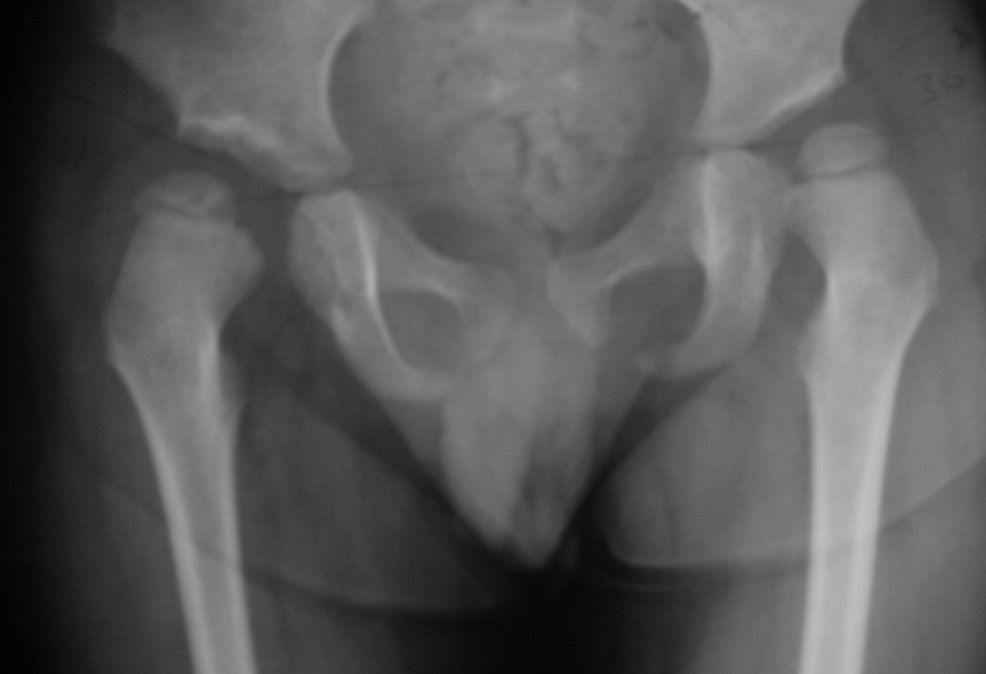

Xray

Dislocated hips in the setting of DDH with ncreased acetabular index